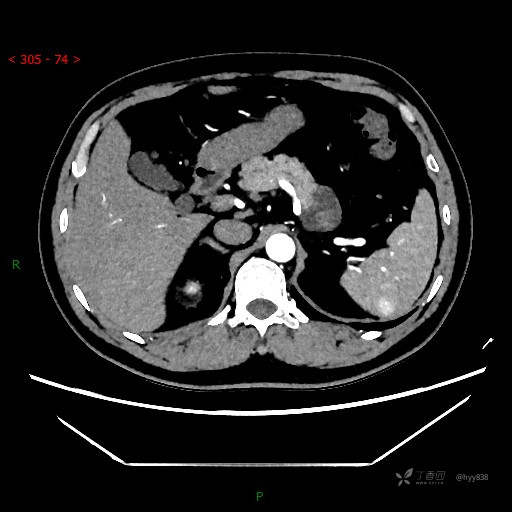

讨论:病变影像特点和性质